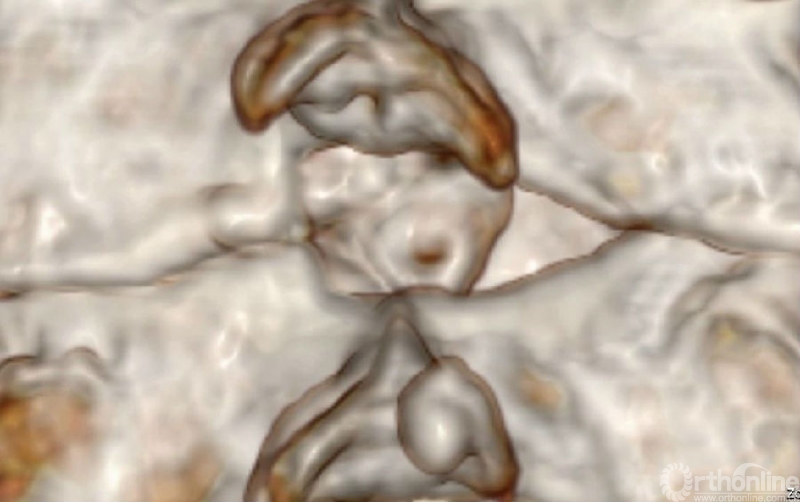

入院查体患者四肢肌张力高,双侧hoffman阳性。CT及MRI检查提示C4/5左侧关节突内缘有一巨大骨块(15mm*16mm),相应节段椎管严重狭窄。椎管内骨块的前端还有一游离骨块。

影像学资料